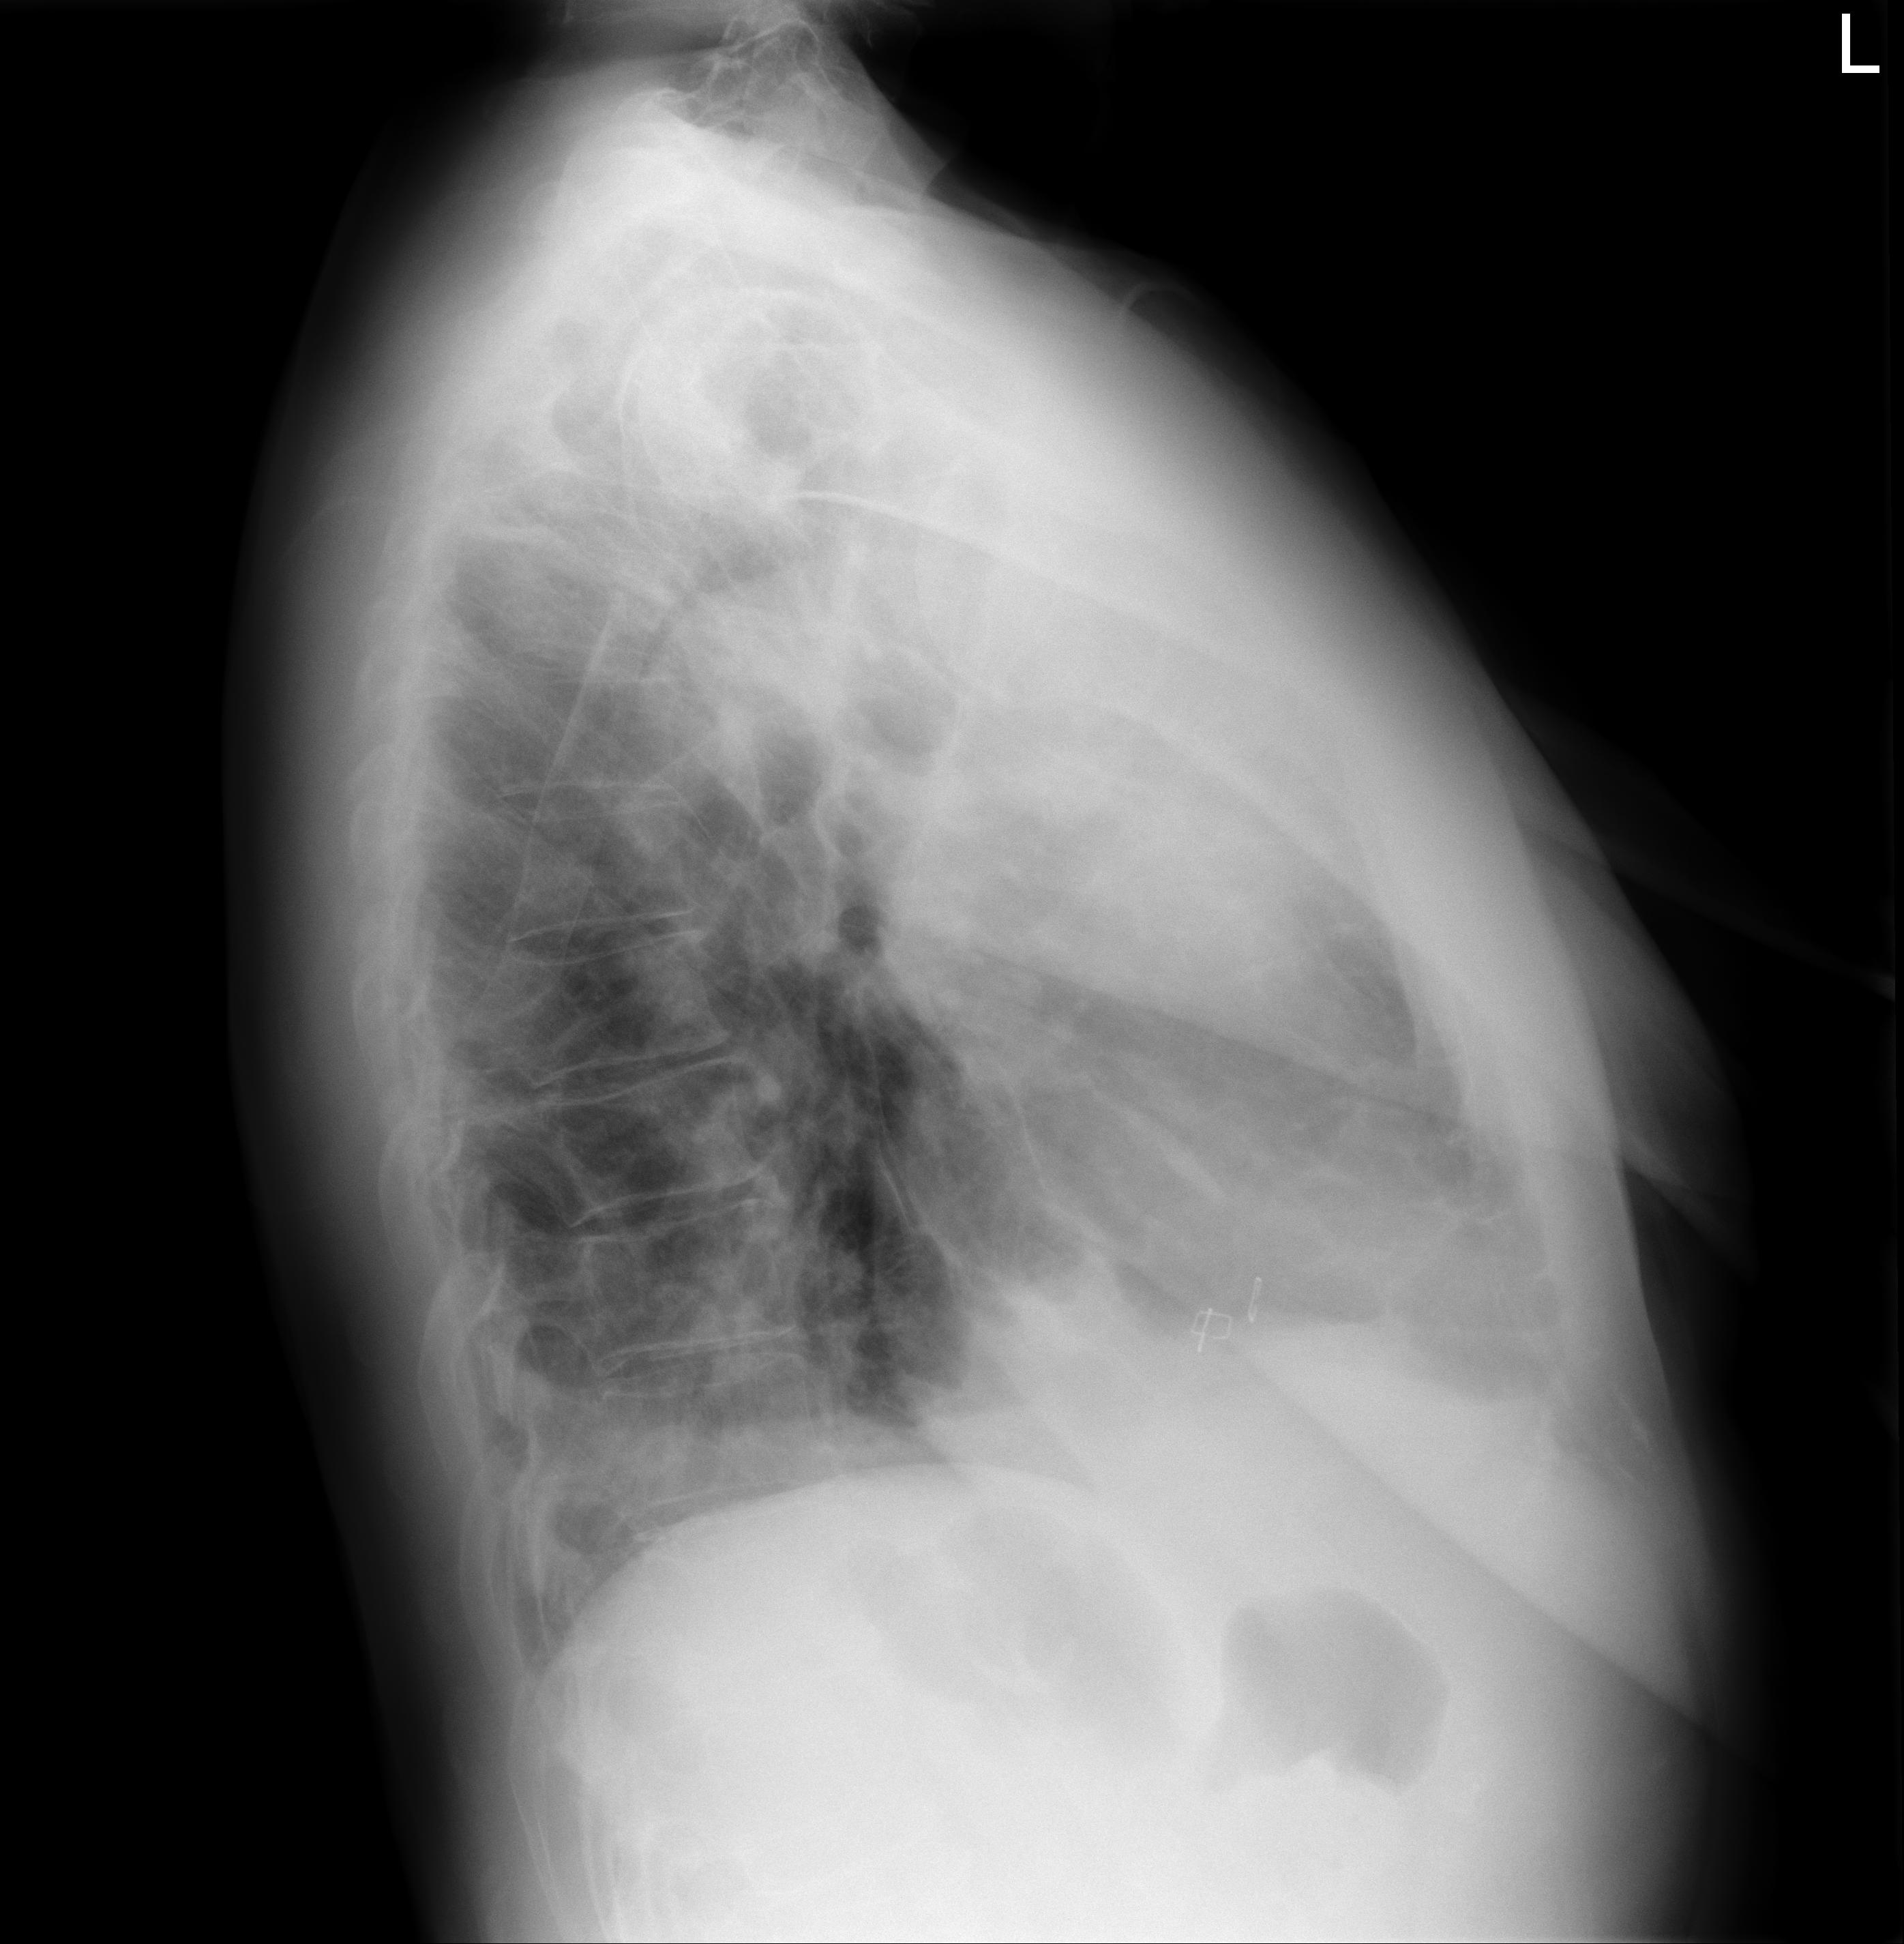

1 Tórax